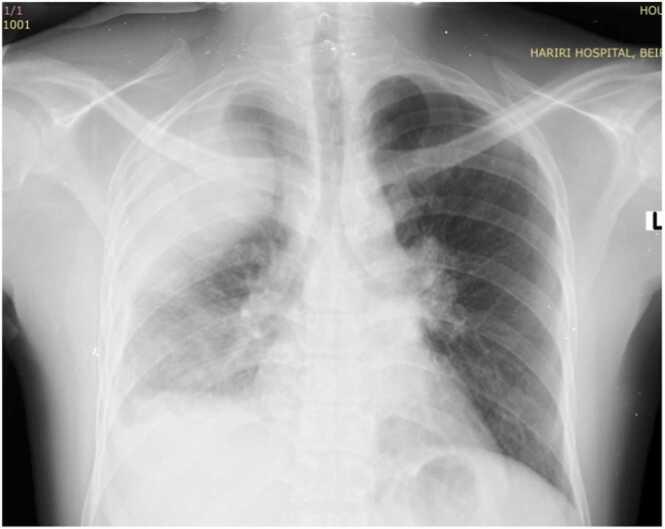

We present a case of 28 years old gentleman, Sudanese, with intermittent fever, non-productive cough, weight loss and night sweats. Chest X-ray then CT chest revealed a large right pleural collection invading the chest wall. Chest tube was inserted, fluid analysis was taken, and a bronchoscopy was done. A diagnosis of Empyema Necessitans was confirmed and patient was started on anti-TB regimen with clinical improvement.

我们报告一例28岁的苏丹男性患者,有间歇性发热、干咳、体重减轻和盗汗症状。胸部X线检查及随后的胸部CT显示右侧胸腔有大量积液并侵犯胸壁。插入胸腔引流管,进行了液体分析,并做了支气管镜检查。确诊为坏死性脓胸,患者开始接受抗结核治疗,临床症状有所改善。